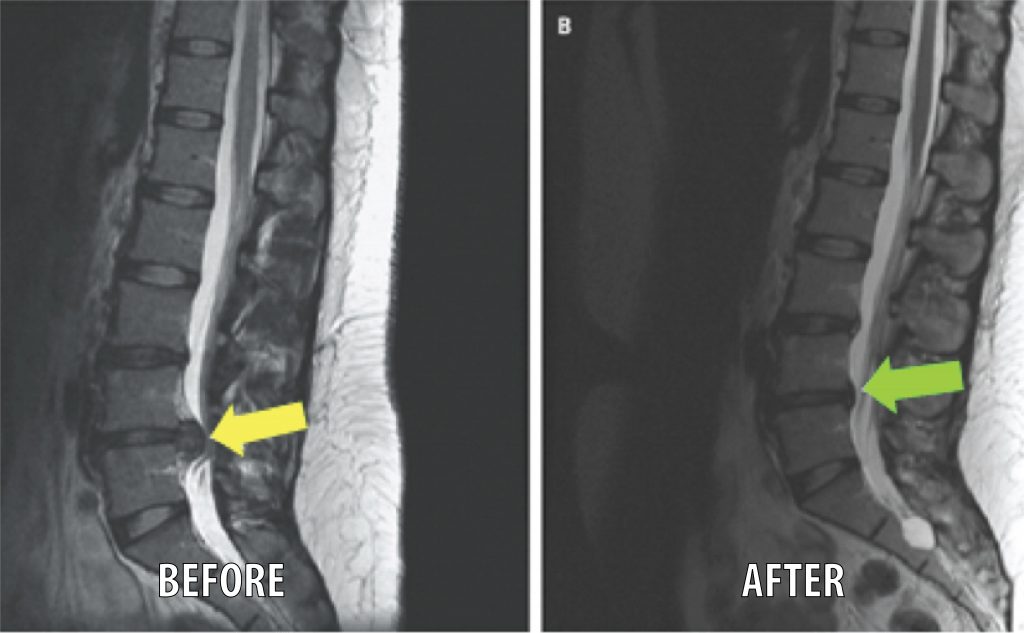

Visual evidence of treatment results including X-rays, scans, and clinical photos

Visual evidence of treatment outcomes

Spinal Decompression Therapy, Flexion/Distraction, Zone Technique/Full Spine Diversified, Arthrostim, Posture Distortion Exercises, At Home traction

Before- Severe low back pain, was told by 4 surgeons he needed surgery, sciatic pain to foot, leg weakness and could not move After- Post Decompression: No low back pain, No sciatic pain, no muscle weakness and back to active life, hiking and traveling Treatment: Spinal Decompression Therapy, Flexion/Distraction, Zone Technique/Full Spine Diversified, Arthrostim, Class 4 Laser, Shockwave, Posture Distortion Exercises, At Home traction

Pre-Decompression Severe Sciatic pain, Severe muscle weakness, Diminished Lumbar reflexes, Severe LBP, could barely sit to perform his job Post Decompression No Sciatic pain, Normal reflexes, No muscle weakness, Minimal LBP, able to perform his duties at work and be an active husband Treatment: Spinal Decompression Therapy, Flexion/Distraction, Zone Technique/Full Spine Diversified, Arthrostim, Class 4 Laser, Shockwave, Posture Distortion Exercises, At Home traction

Pre-Decompression L4 Herniation with Severe Sciatic pain, Severe muscle weakness, Diminished Lumbar reflexes, Severe LBP, could barely sit to perform his job Post Decompression No Sciatic pain, Normal reflexes, No muscle weakness, Minimal LBP, able to perform his duties at work and be an active husband Treatment: Spinal Decompression Therapy, Flexion/Distraction, Zone Technique/Full Spine Diversified, Arthrostim, Class 4 Laser, Shockwave, Posture Distortion Exercises, At Home traction